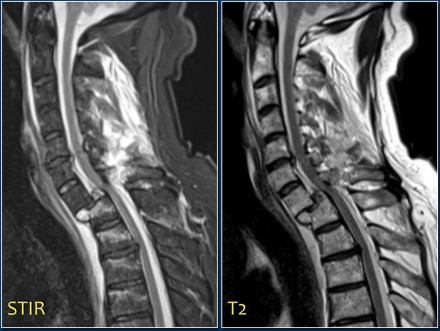

The images are of a patient with a typical bamboo spine as a result of ankylosing spondylitis.

After a fall on his back no fracture was seen on the x-rays.

However the CT shows a thin fracture line through the anterior side of the vertebral body and also through the spinous process.

Continue with the MR-images.

Look at the images.

What are the findings?

Then scroll to the next images.

The findings are:

- Vertebral bodies show marrow edema as a result of a fracture.

- Torn flaval ligament (yellow arrow).

- Fractures through the posterior elements (red arrows).

The TLICS-score is high, because there is distraction and injury to the PLC.